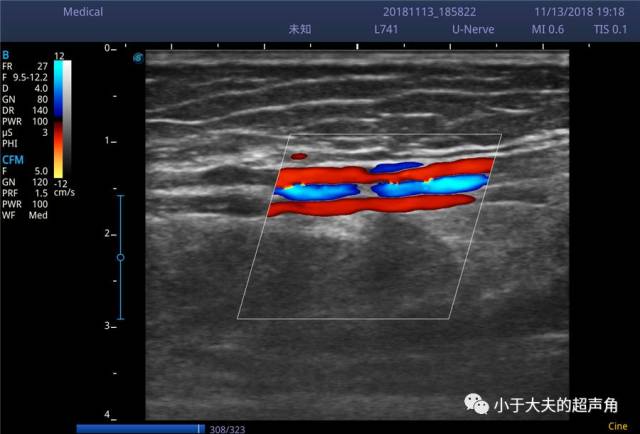

cdfi:胫后动脉与伴行的两条胫后静脉一同组成 "夹心饼",红蓝相间